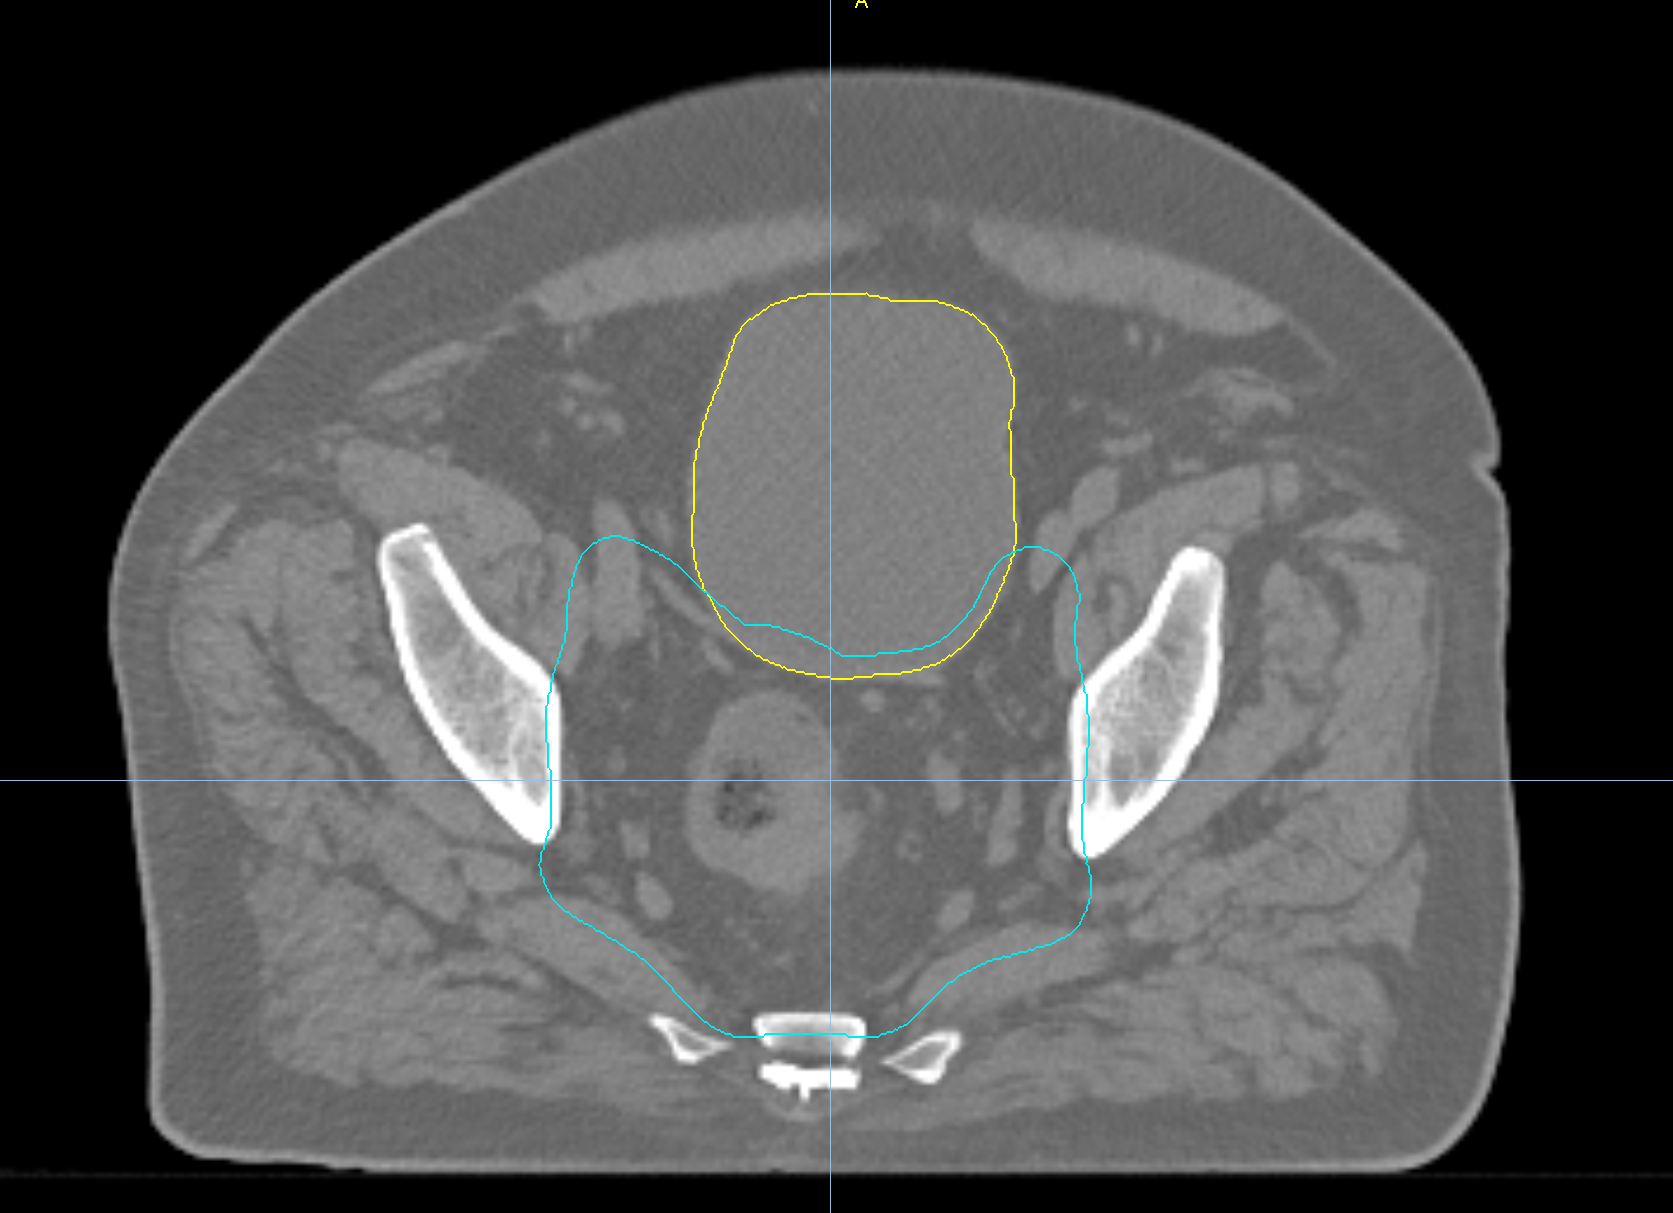

Left Breast with Deep Inspiration Breath Hold

< View All Plan Studies RADIXACT SYSTEM Left Breast with Deep Inspiration Breath Hold Case History AGE: 76-year-oldGENDER: Male Medical History Immidiate tolerance: Grade II dermatitis with eyelid edema, Grade I conjunctivitis resolved with Sterdex Diagnosis: Squamous cell carcinoma of the right lower eyelid Planning CT Images Treatment Plan Images